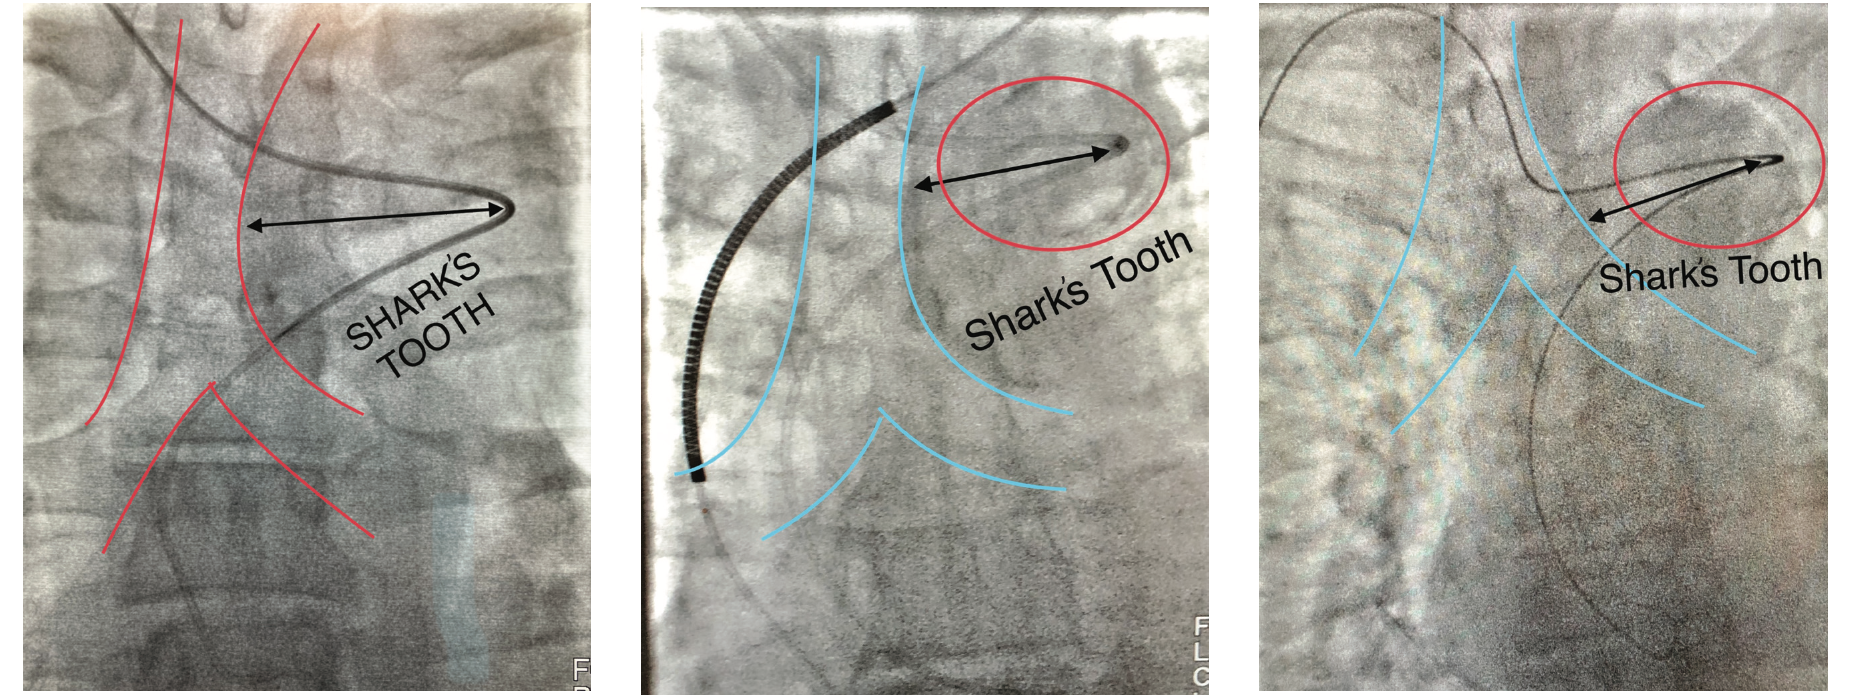

The “Shark’s Tooth”

With “standard” right subclavian tortuosity, the catheter crosses the right to left side of the trachea and has a rounded out shape (Figure 2B). Catheters also move inferiorly for a few centimeters before moving back right towards the trachea again, prior to reaching the sinotubular junction. In contrast, with an aberrancy, the catheter crosses the trachea and travels significantly left past the trachea and abruptly turns back to the right, towards the transverse and ascending aorta that is delineated quite well with an left anterior oblique (LAO)/caudal view. The catheter may also follow a superior trajectory before reaching and/or cannulating the coronary ostia (Figure 3).

Radiographically, all have a similar appearance (Figures 5-8). They move left across the trachea, well into the lung field, and make an acute trajectory change back to the right, towards the transverse and ascending aorta. This abrupt course of the catheter change resembles a “shark’s tooth” and as a radiographic sign, may offer the clue of an aberrant subclavian. Different wires may enable easier negotiation into the ascending aorta. Wholey wires (Medtronic) may be used because of their soft tip and strong shaft. Hydrophilic wires such as Glidewires (Terumo) are also used to navigate through the aberrancy. Keeping an Amplatz super stiff wire in the catheter may help provide the necessary support for selective coronary angiography. Even if operators get close to the coronary ostia, tension and energy built up in the catheter can disallow selective engagement and force a bailout to the contralateral radial or the femoral approach. Conversely, there are times in the presence of this ominous anatomy when catheters will engage quicker than the operator can do a “time out.” A skillful operator might display some “catheter legerdemain” to negotiate these problems; however, a little bit of luck also goes a long way. One doesn’t necessarily have to be a funambulist to recognize and selectively cannulate the coronaries.